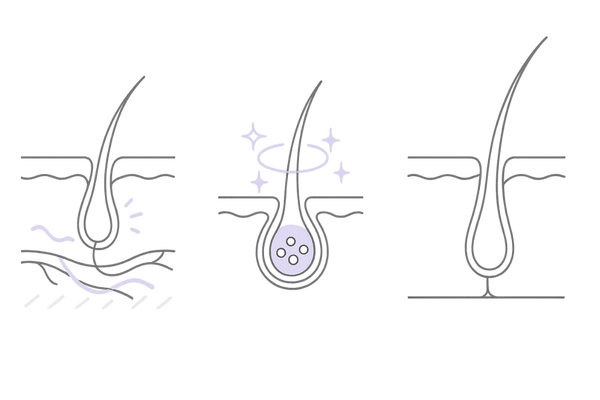

髪の毛には「成長期」「退行期」「休止期」という一連の周期、いわゆる「ヘアサイクル」があります。

薄毛は、このヘアサイクルのうち「成長期」が短くなり、髪が太く長く成長する前に抜け落ちてしまうために進行します。

ミノキシジルは休止期にある毛包に働きかけ、新たな成長期へと移行するのを促す作用を持ちます。

この働きにより短くなってしまった成長期を正常な長さに戻し、細く弱々しい髪の毛を太く健康な髪へと育て直す手助けをします。

休止期の毛包を成長期へ導く

ミノキシジルの最も重要な働きのひとつが、活動を休んでいる毛包(休止期毛包)を刺激し、再び髪を成長させる段階(成長期)へと誘導することです。

薄毛が進行している頭皮では、多くの毛包が休止期のまま留まっています。

ミノキシジルは、これらの眠っている毛包を目覚めさせ、新たな髪の毛を生やす「スイッチ」を押す役割を果たします。

毛母細胞の活性化と血管拡張作用

髪の毛は、毛根の一番奥にある毛母細胞が分裂を繰り返すことで作られます。

ミノキシジルは、この毛母細胞に直接作用し、細胞分裂を活性化させます。同時に、毛根周辺の毛細血管を拡張させて血流を増やす働きも持ちます。

この二つの相乗効果により、髪の成長に必要な酸素や栄養素が毛母細胞へ豊富に届けられ、より強く太い髪の毛が育つ環境を整えるのです。